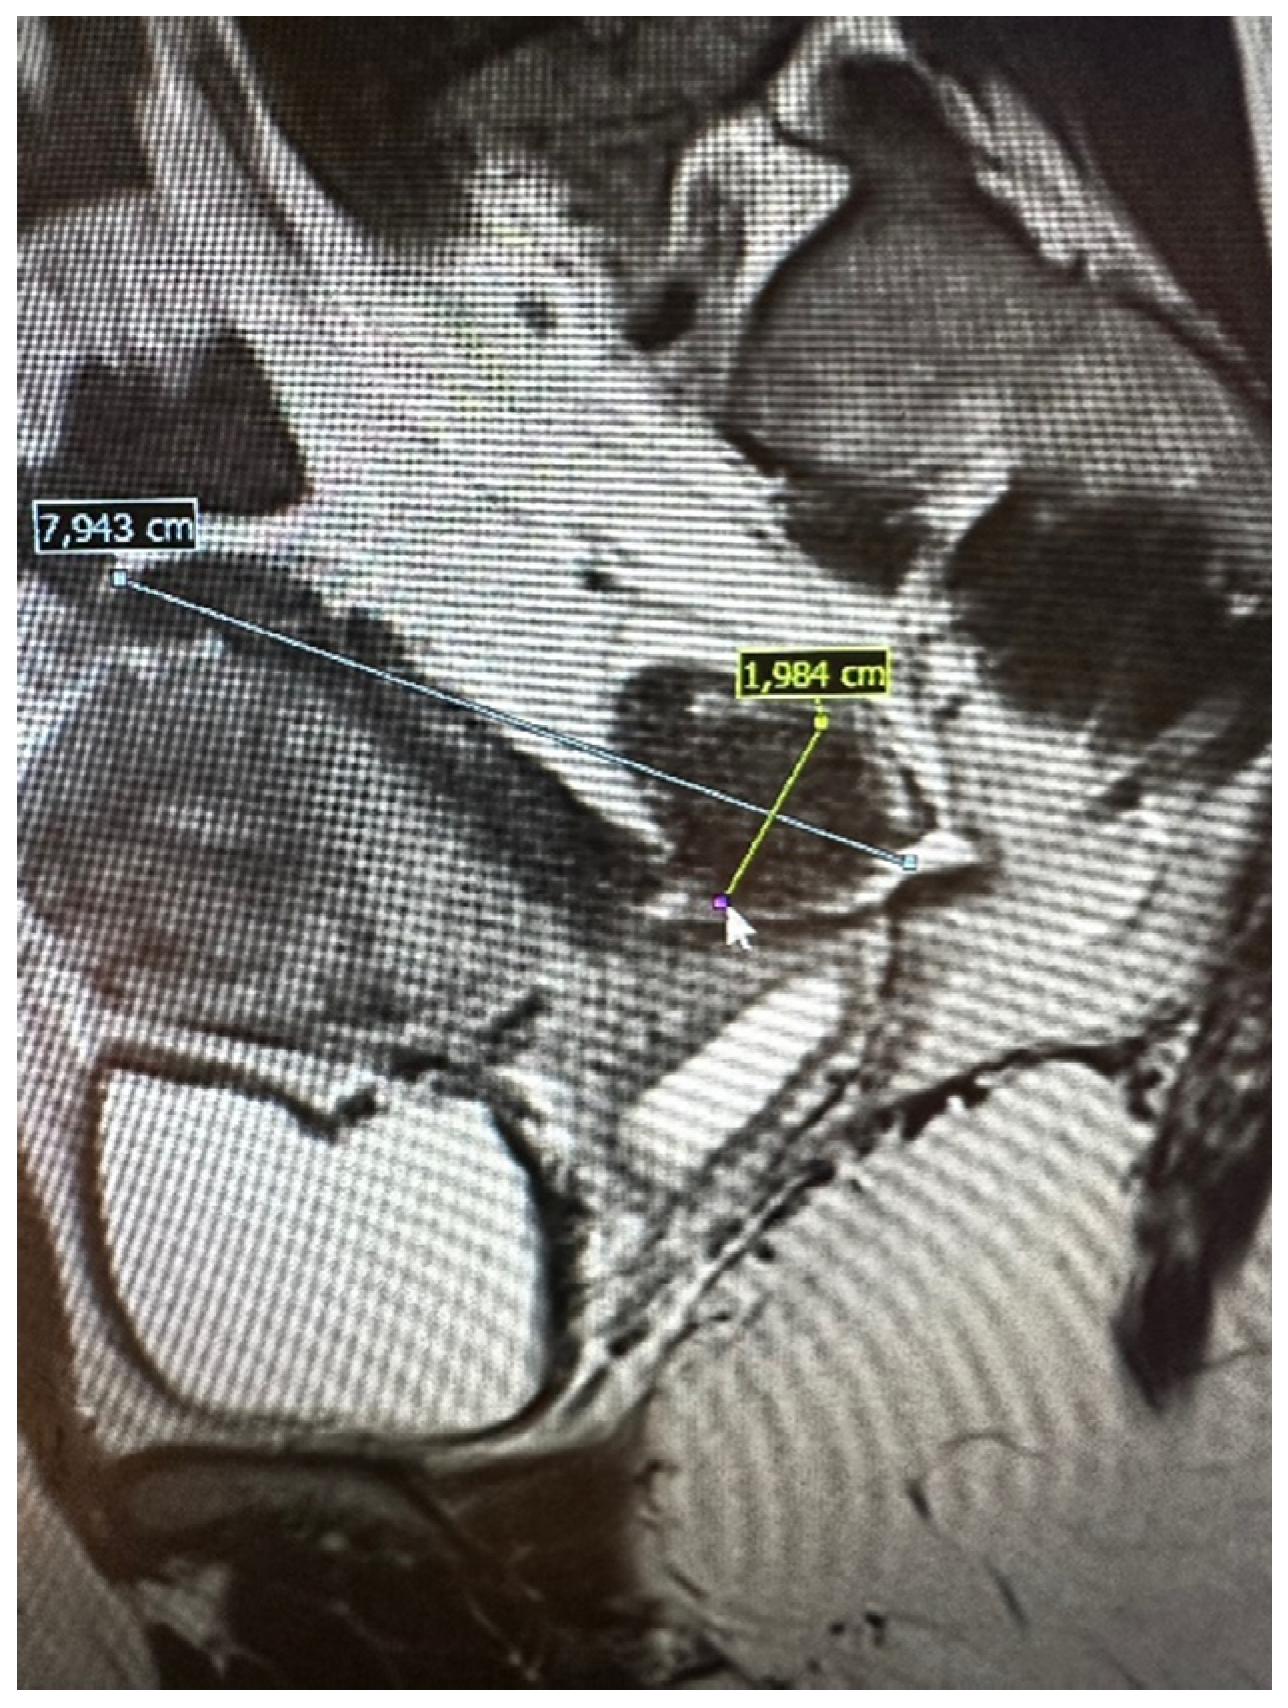

The pelvic MRI was conducted using a 3T scanner, following the established protocol for endometriosis. This included scans before and after the intravenous administration of a gadolinium-based contrast agent, as well as contrast administration into the vagina (using hyaluronic acid gel and a vaginal tampon) and rectum (using a water solution). Patients were positioned supine with a moderately filled bladder and received an intravenous anti-peristaltic agent (butyl-scopolamine). The procedure was performed following bowel preparation (BPP) and fasting the previous day. The examination typically lasted approximately 60 min. The report included the abdominal wall structures. An example of an MRI scan is shown in Figure 2.

Figure 2.

Preoperative magnetic resonance examination. The same bowel DE nodule as presented in TVS above (compare Figure 1).